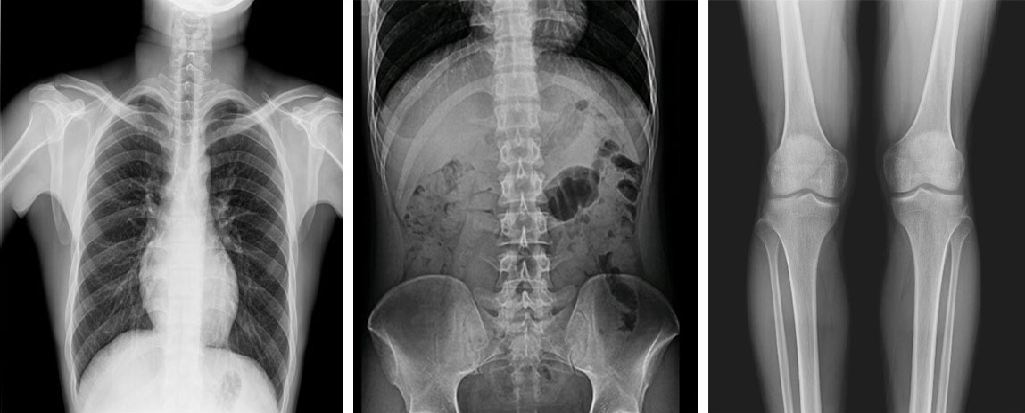

與此同時(shí),動(dòng)態(tài)DR的成像視野與精度也勝于靜態(tài)DR。動(dòng)態(tài) DR17×17 英寸方形幅面進(jìn)行動(dòng)態(tài)成像,能夠?qū)鹘y(tǒng)動(dòng)態(tài)造影幅面小的問題全部解決,同時(shí)由于幅面較大,臨床操作技師能夠在一個(gè)大的幅面下觀察診斷,當(dāng)看到病變部位時(shí)實(shí)時(shí)高清點(diǎn)片,從而很好地捕捉到病變點(diǎn),也大大降低了檢查時(shí)間。

PLD8000系列數(shù)字透視攝影系統(tǒng)集數(shù)字化攝影、數(shù)字化透視、數(shù)字化造影、可視化點(diǎn)片等多種功能于一體,搭載高品質(zhì)高壓發(fā)生器、球管與平板探測(cè)器,確保性能穩(wěn)定的同時(shí)成就高清成像,同時(shí)提高機(jī)架自動(dòng)化程度,并且配備智能化電動(dòng)床體,帶來智能化、人性化操作體驗(yàn),全面滿足各級(jí)醫(yī)療機(jī)構(gòu)放射檢查需求。